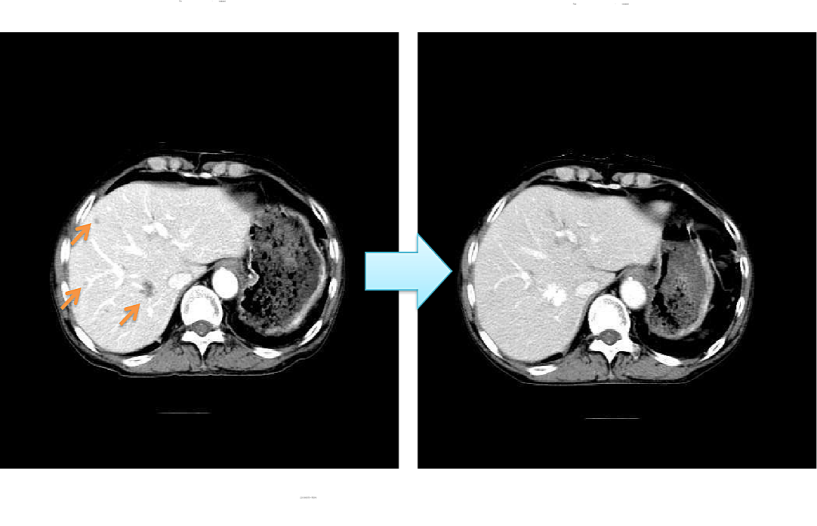

Effect of rAd-p53+ RAD-p53-DC +LAK in the treatment of liver metastasis of non-small cell lung cancer (1 course: 3 injections of immune cells)

The images clearly showed that after Gendicine combined with immune cell therapy, the three metastatic lesions of the liver

completely disappeared, and the effect was significant.